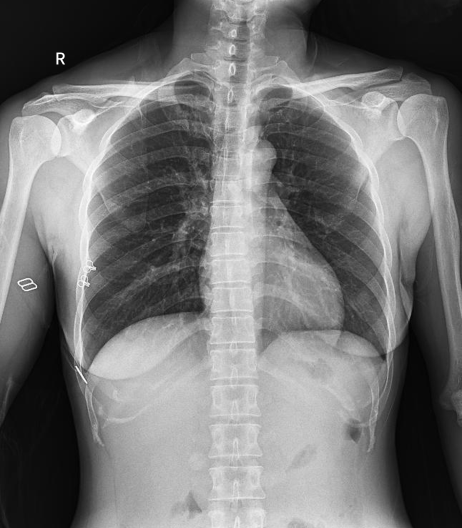

普利德醫療自主研發的新一代數字化X線透視攝影系統,可應用于DR攝影、數字透視、數字造影以及可視化精準DR拍片等多種臨床X線檢查領域。

● 17*17英寸的超高清像素動態平板探測器,更大的視野范圍,無需移動即可觀察整個動態過程,避免拖尾、噪聲對圖像的影響;

● 高效動態平板技術,圖像不會有幾何畸變,提供高分辨率和精確的圖像,為醫生臨床診斷提供精準依據;

● 最高幀速可達30幀/秒,動態采集清晰流暢,避免漏診、誤診情況的發生;

● 在可視過程或回放過程中,如發現疑似病灶,可進行毫秒級高清點片,隨時抓取單幀圖像,精準捕抓病灶。